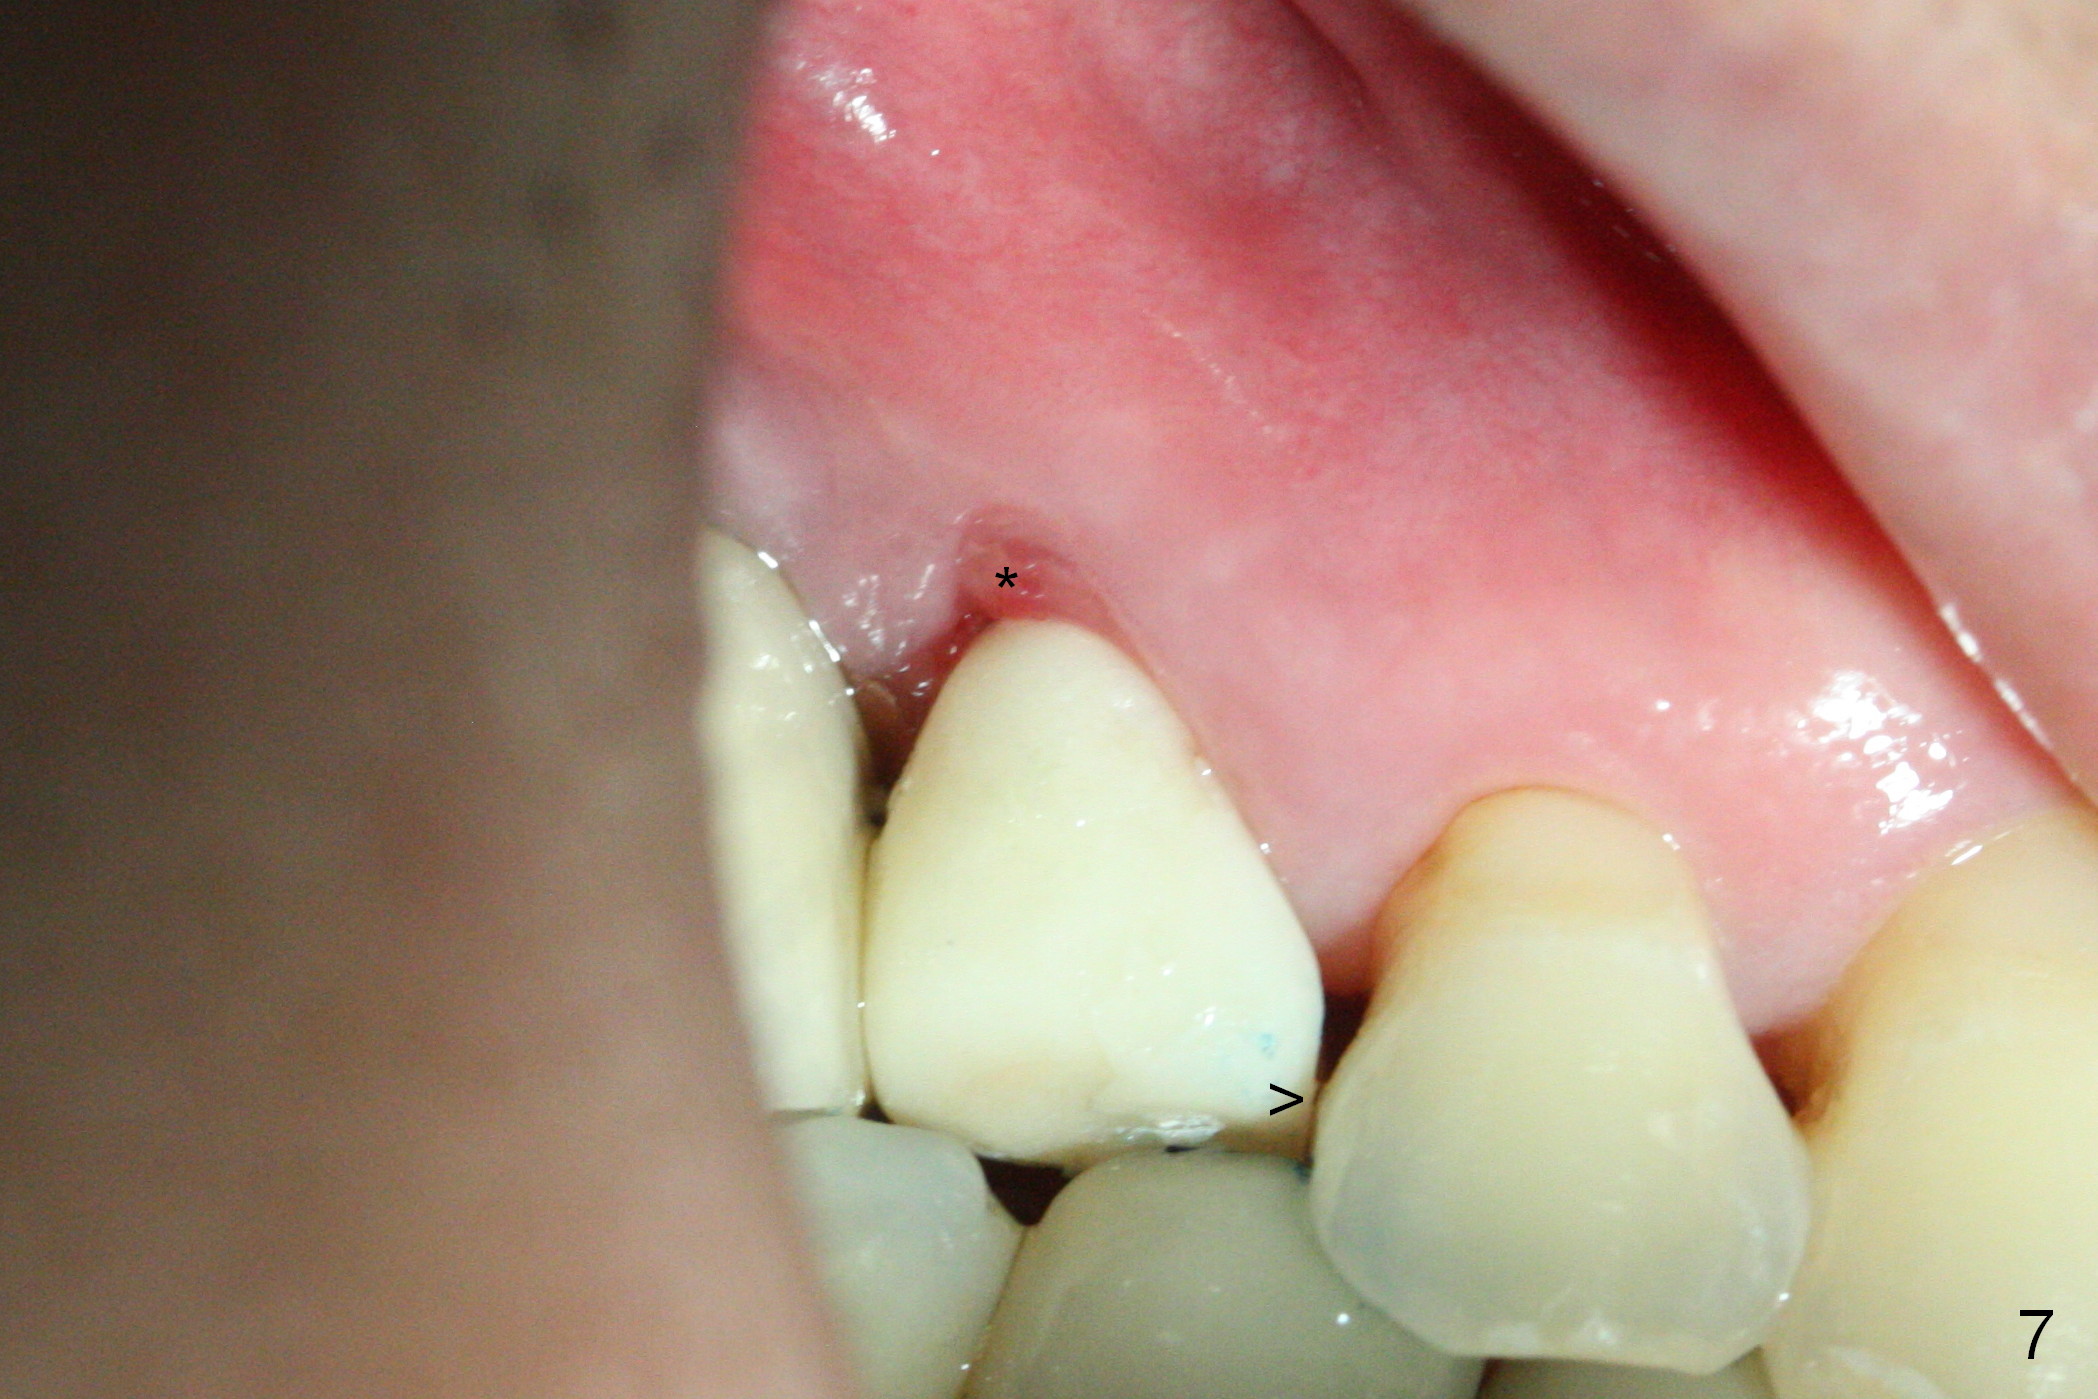

These are done 3 weeks postop (Fig.7) with granulation tissue having formed (*).  The teeth #14 and 18 become symptomatic 4 weeks postop.

The distal papilla reforms buccally (Fig.8 *) and palatally (Fig.9) 4 months postop.  It appears that the 4 mm cuff of the pair abutment (Fig.10 >) is apical to the mesial crest (*).  The distal coronal implant threads seem to be covered by bone graft (Fig.11 <).  Therefore pair abutments with 5 mm or more cuff are required in cases of the uneven bone.   Implants have to be placed deep.  CT taken 3 months post cementation (10 months postop) shows that the implant is placed in the middle of the alveolus without apparent thread exposure.  CT taken 1 year and 8 months post cementation (Fig.13) shows that the implant is placed in the middle of the alveolus without apparent thread exposure, as compared to those at #2 and 3, which are placed buccal (B).